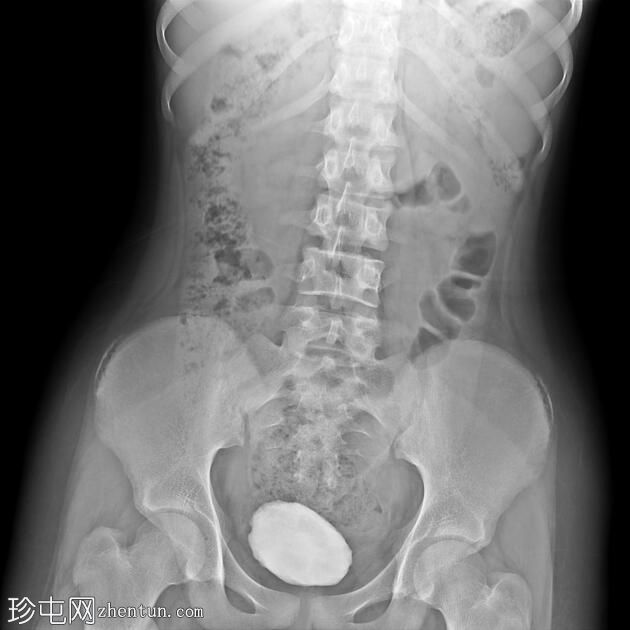

年龄:12岁

性别:女

透视检查

正位

排尿性膀胱尿道造影显示尿液反流至

肾脏

,伴有输尿管和肾盂肾盏系统轻度扩张。

还观察到排尿后残余尿。

本病例描述了一例有复发性尿路感染病史的儿童,其双侧3级膀胱输尿管反流。